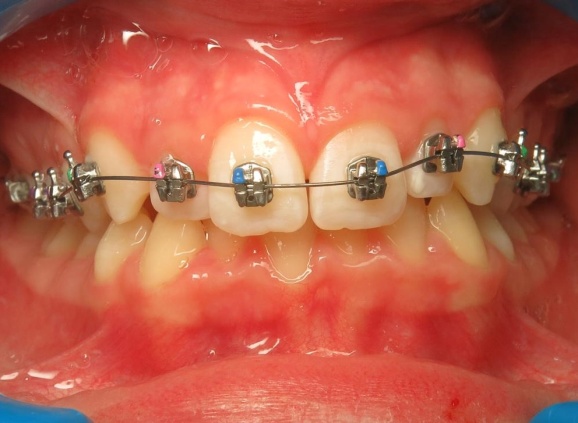

3 - Phase 2 : traitement orthodontique- alignement des dents et occlusion

Le traitement a d’abord consisté à corriger le décalage entre les bases osseuses des mâchoires par une phase orthopédique. Une fois cet équilibre rétabli, un appareil multiattaches a été mis en place pour aligner les dents sur des bases désormais bien positionnées. La dernière étape a permis de peaufiner les contacts entre les dents afin d’obtenir une occlusion fonctionnelle et stable.